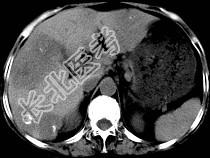

- 单项选择题女,55岁, 腹胀,肛门闭气, 消瘦乏力,肝区疼痛, CT检查如图,最可能的诊断为 ( )

A、多发性肝脓肿

B、肝癌肝内转移

C、肝淋巴管瘤

D、肝脏囊腺瘤

E、结肠癌肝转移